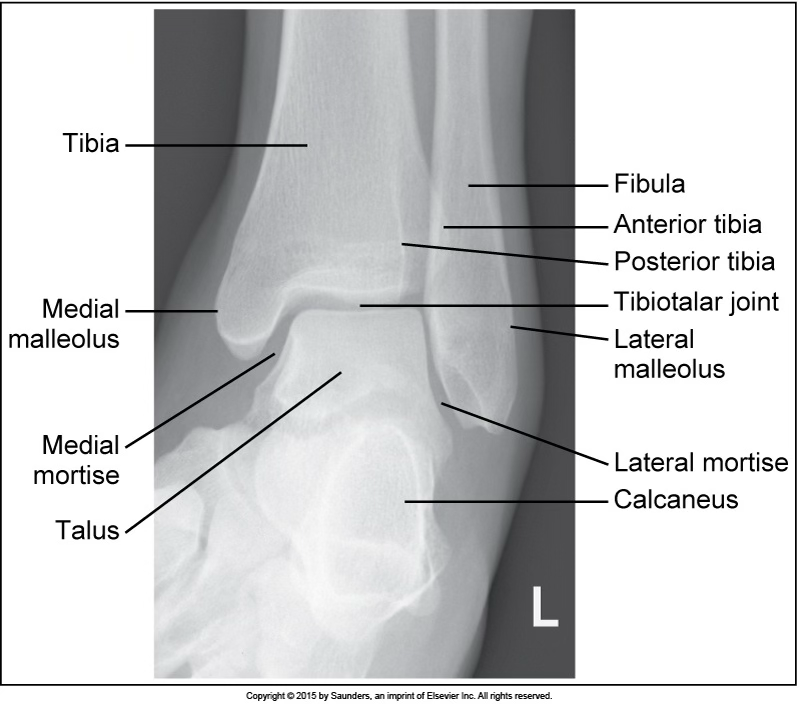

AP oblique ankle (mortise)

accurate positioning